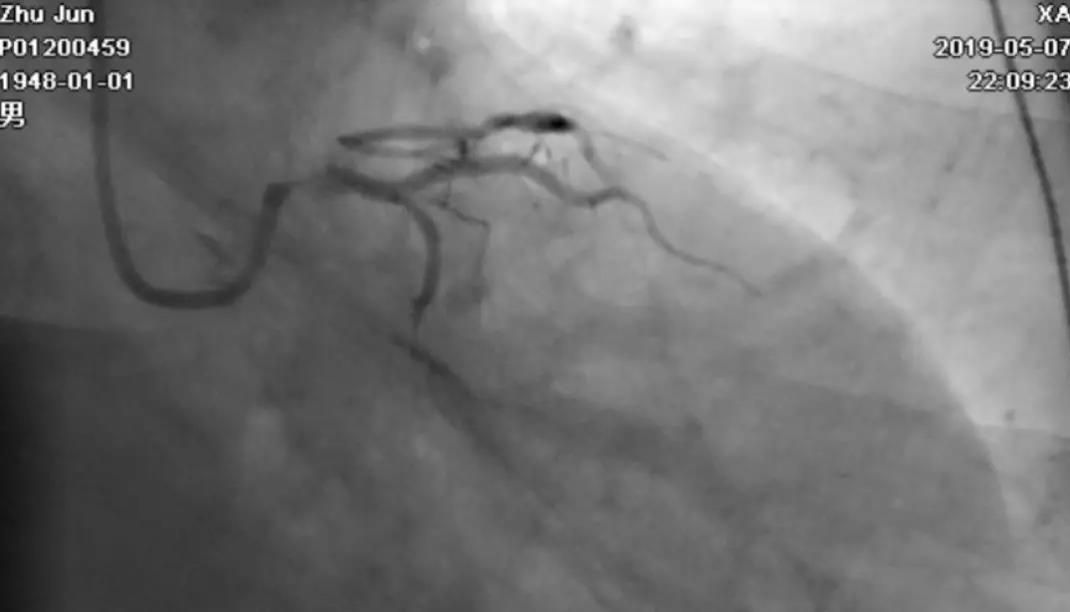

轻轻冒烟,证实指引导管到位

轻轻冒烟,大致了解前降支的情况

导丝分别进回旋支和前降支